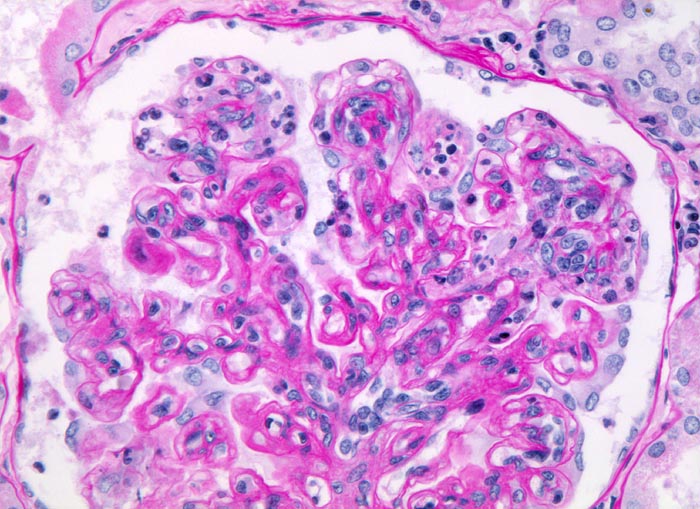

PathoPic – image database / PathoPic ID 4995 - membrano-proliferative Glomerulonephritis Typ I

membrano-proliferative Glomerulonephritis Typ I

Geringe Verbreiterung des Mesangiums mit deutlicher Zellvermehrung (Mesangiumzellkerne überlappen einander, mehr als 3 Mesangiumzellen pro Mesangiumfeld). Die Kapillarschlingen enthalten zahlreiche neutrophile Granulozyten und Monozyten. Die peripheren Basalmembranen sind stellenweise deutlich verdickt bzw. verdoppelt.

Nephrotisches Syndrom, Mikrohämaturie und arterielle Hypertonie. Chronische Hepatitis C.

Der Nachweis von Granulozyten und Monozyten in den Kapillarschlingen und die mesangialen Veränderungen lassen differentialdiagnostisch an eine endokapilläre Glomerulonephritis denken.